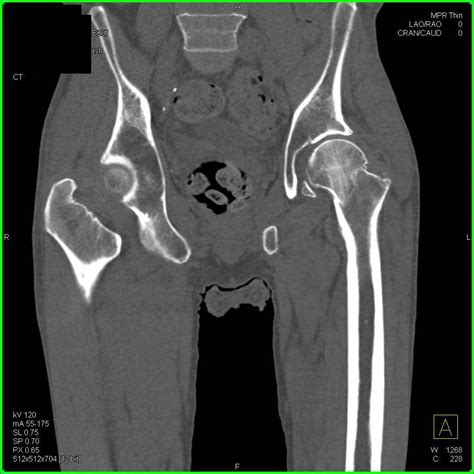

Diagnosing impacted bone fractures involves a combination of physical examination and imaging tests. The diagnostic process typically includes:

• CT Scans: Computed tomography (CT) scans for more detailed images, especially in complex fractures.